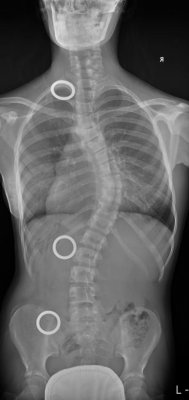

Příčina vzniku skoliózy - zakřivení páteře do strany s porušením všech rovin páteře - není doposud zcela objasněna. Tradiční operační metody napravení zakřivení páteře dospívajících dětí (mezi 11. - 16. rokem) vyžadují při operační nápravě následný pevný kostěnný srůst obratlů v celé délce deformity bez možnosti pooperačního normálního pohybu obratlů a bez možnosti jejich dalšího přirozeného růstu.

Nová metoda umožňuje nejen téměř dokonalé napravení deformity, ale současně zajišťuje i další přirozený růst obratlů a nabízí i unikátní techniku udržení pohyblivosti operované páteře. Nový typ instrumentace přináší maximální šetrnost ke tkáním operovaného dítěte a lepší výsledný kosmetický efekt. Velmi významným faktorem je i výrazné zvýšení bezpečnosti samotné operace, která vyžaduje méně implantovaného kovového materiálu.

Celkově nová metoda zajišťuje nápravu dětských skoliotických zakřivení páteře s výsledkem výrazně se blížícím neoperované rovné páteři.